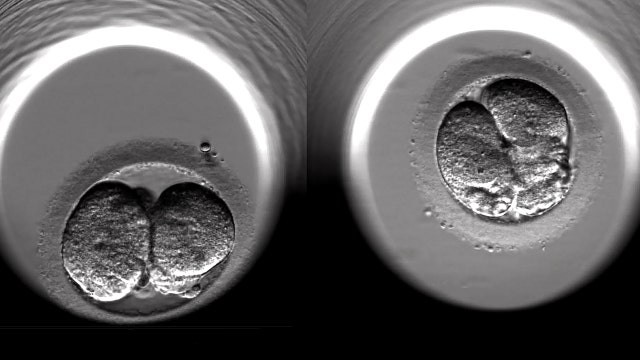

What a time to be alive: Reproductive breakthroughs of the 2010s that changed life as we know it

Some of the scientific advancements of the 2010s have been truly mind-blowing, and perhaps none more so than the leaps and bounds we’ve made in the realm of reproduction.